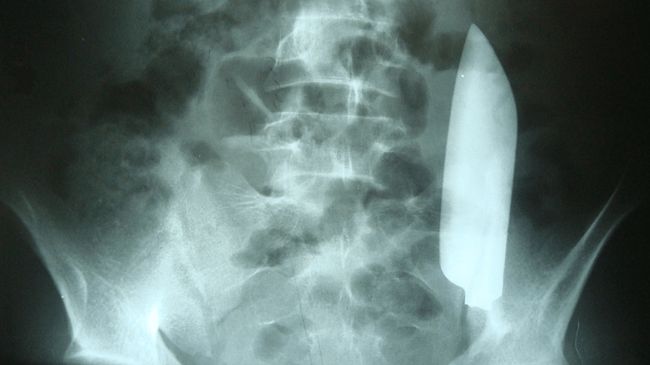

Pisau menyangkut di perut pria di Nepal. (Foto: Cureus Journal of Medical Science).

Kemudian, dokter langsung melakukan rontgen untuk bisa memeriksa lebih lanjut. Betapa kagetnya, sang dokter menemukan ada sebilah pisau yang bersarang di perutnya.

Pisau itu melintas dari sisi kanan ke kiri perutnya. Akan tetapi, menurut laporan kasus di jurnal Cureus, pisau itu tidak melukai organ dalam lainnya.

Hal yang menakjubkan lainnya, pada kasus pria ini pisau itu berpindah dari sisi kanan ke kiri tanpa menyebabkan cedera tambahan.

Dari hasil rontgen, ditemukan ada luka di bagian liver pria tersebut. Namun, itu diperkirakan terjadi akibat penikaman sebelumnya, bukan di saat kejadian yang dilaporkan jika dilihat dari lokasi luka tusuk tersebut.

Terdapat sedikit darah yang ditemukan di dalam tubuh pasien. Selain itu, tidak ada isi usus, yang menunjukkan bahwa pisau itu tidak menusuk saluran pencernaan, dan ia tidak memiliki tanda-tanda peritonitis.